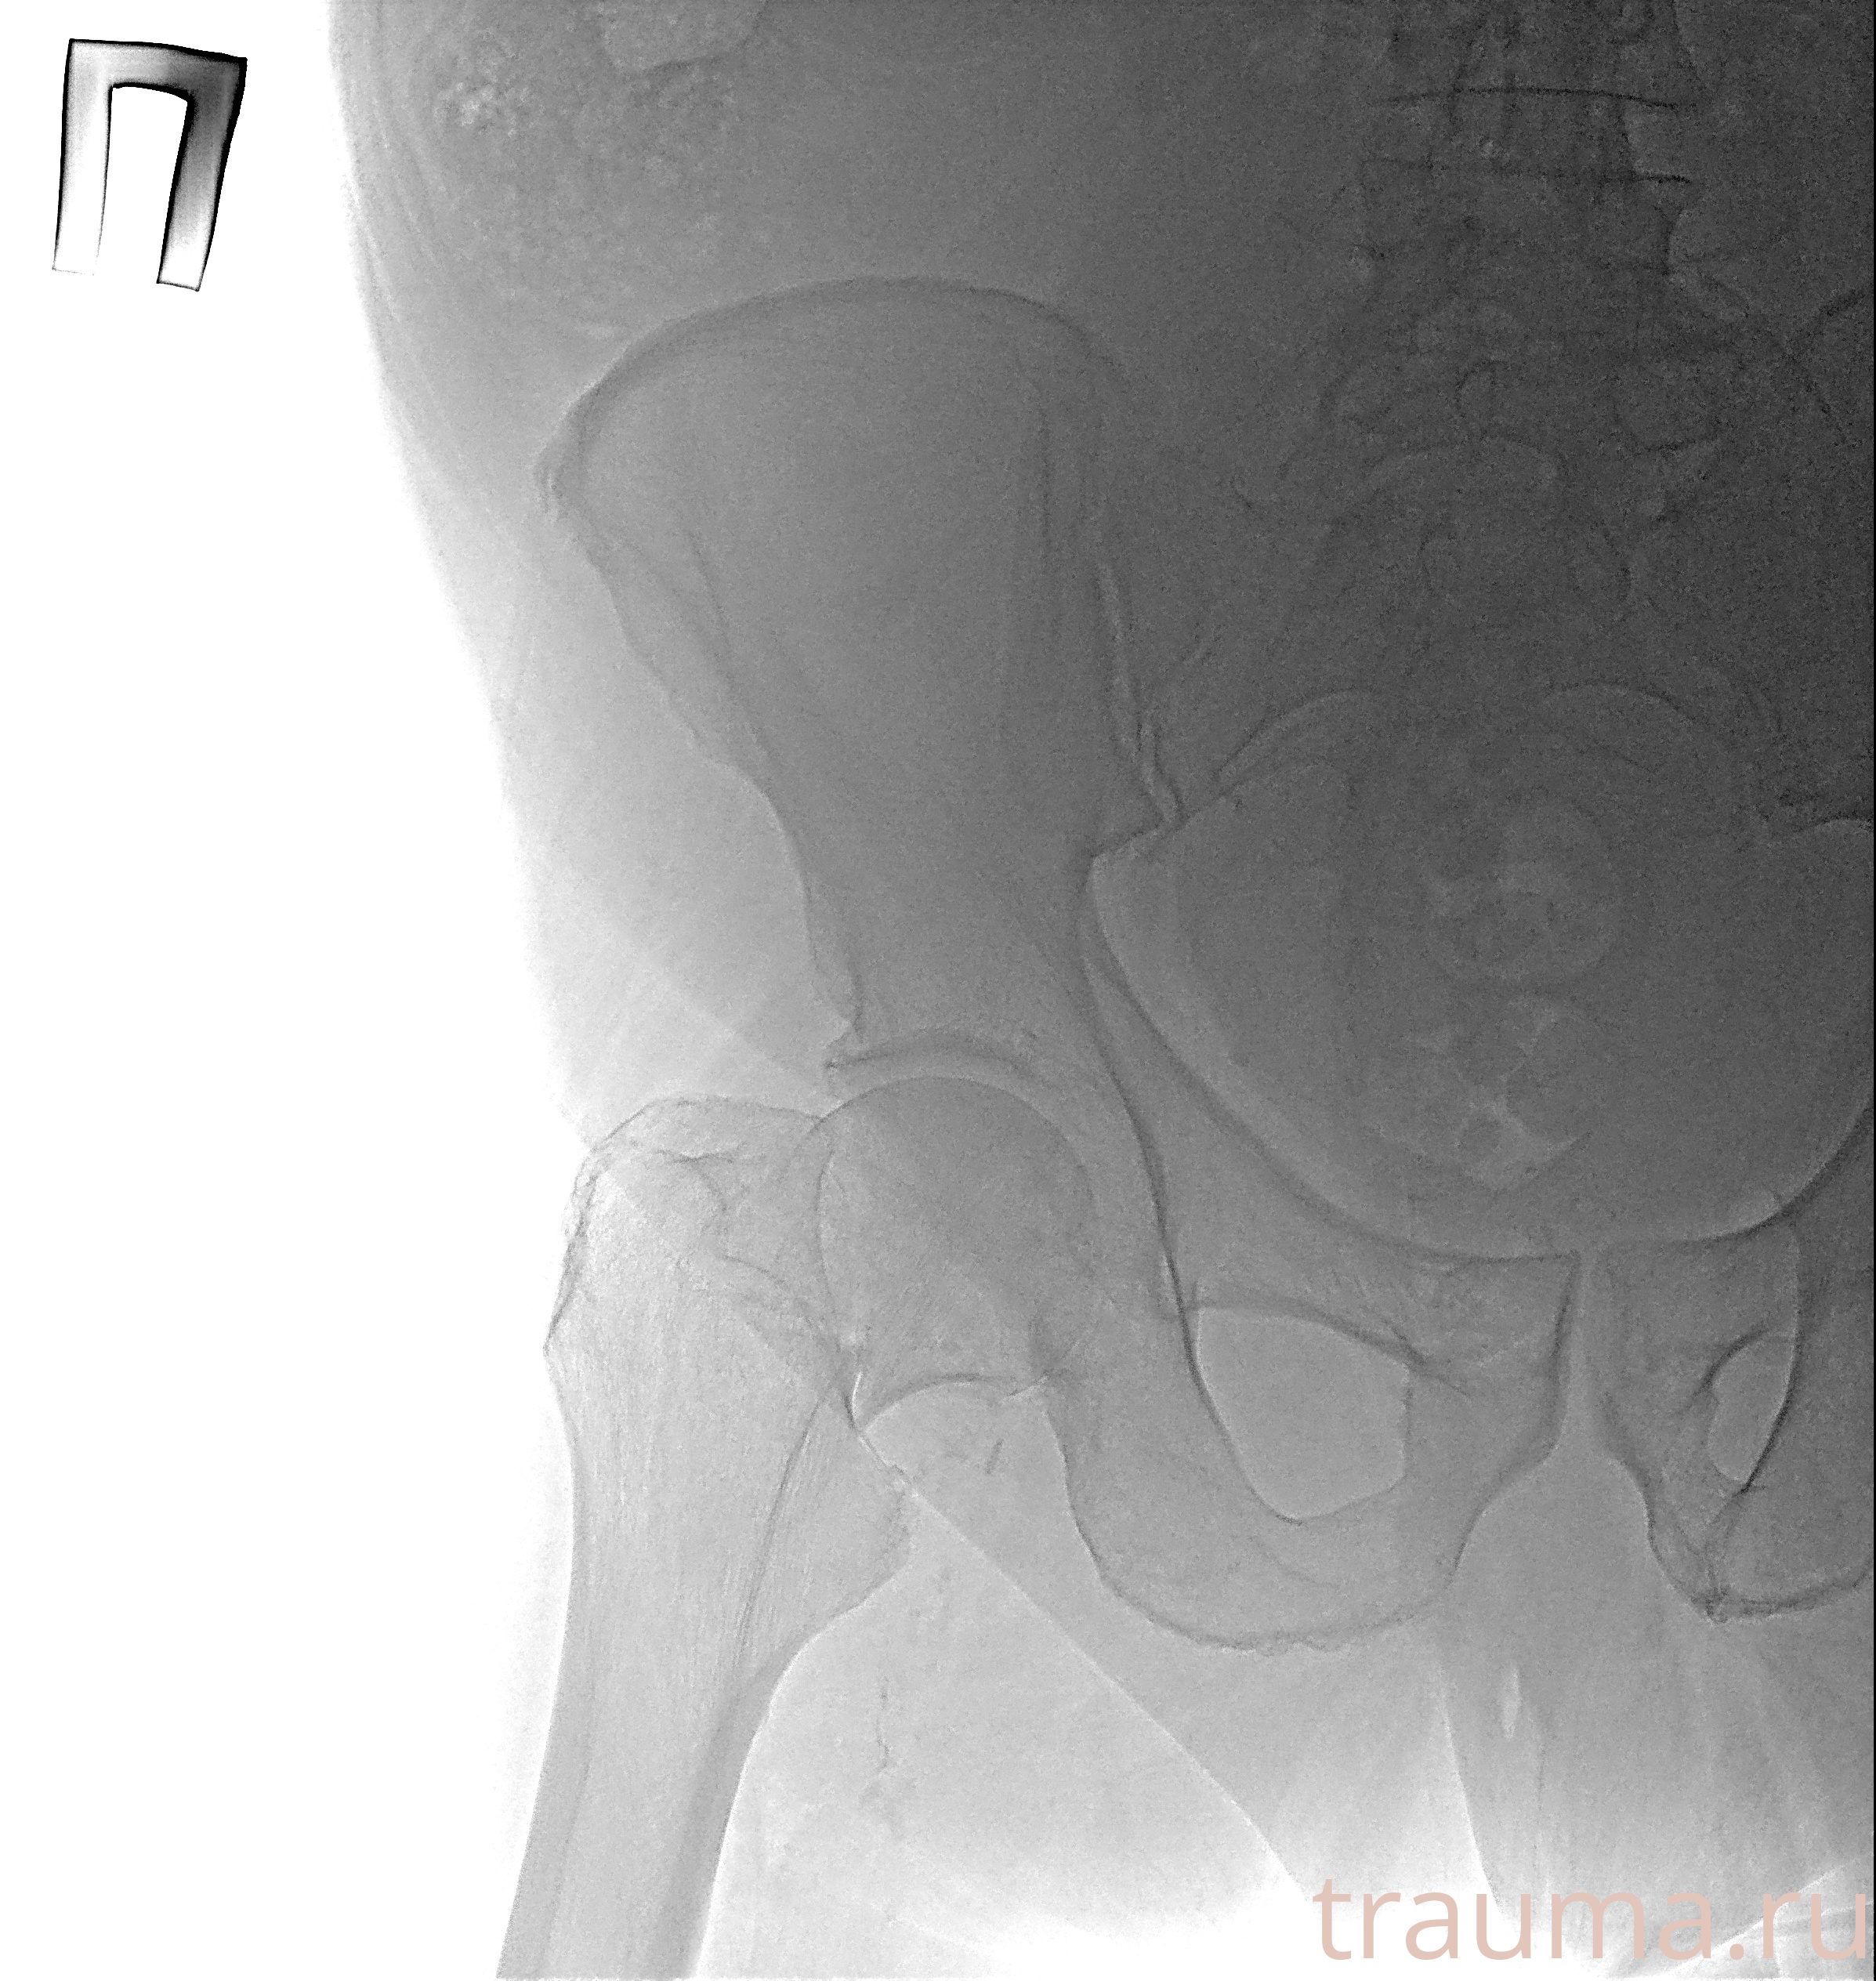

Рентгенограммы

Рентген на дому: по вашему адресу приезжает врач-рентгенолог, травматолог-ортопед с мобильным рентгеновским аппаратом, проводит диагностику травмы или заболевания, делает необходимые рентгенограммы, дает рекомендации по дальнейшему лечению. Получить качественные снимки в домашних условиях возможно благодаря уникальной методике, разработанной МосРентген Центром для института  Склифосовского